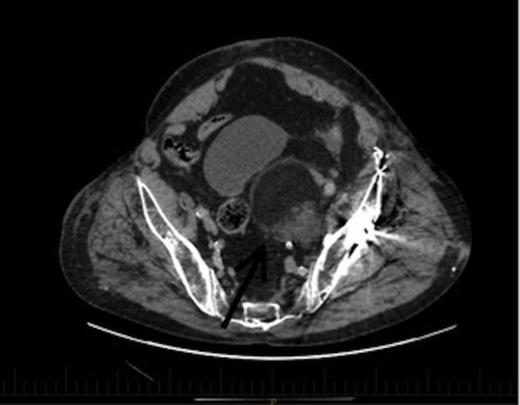

An axial section of the CT demonstrating a 6.7x6cm.3x7.3cm left pelvic lesion adjacent to the trauma site. Arrow denotes the EMH lesion

A CT scan demonstrated a 6.7x6.3cmx7.3cm well-defined left pelvic mass immediately medial and adjacent to the left acetabulum compressing the bladder and the iliac vessels. The mass was heterogeneous in density comprising of both muscle and fat with no calcifications. He underwent a repeat staging-CT, MRI, whole body thallium scan, and a CT-guided biopsy. The MRI scan confirmed a lobulated well-circumscribed mass with a heterogeneous T1 and T2 appearance. Areas of hyperintensity reported on CT corresponded to fatty components within the mass, while the rest of the mass appeared relatively hypointense to skeletal muscle, and was thought to be consistent with a liposarcoma. The Single Photon Emission Computed Tomography (SPECT) scan demonstrated low-grade activity in the mass and the staging-CT did not reveal any signs of malignancy. A confirmatory CT-guided biopsy however diagnosed the mass as EMH tissue, while a CT angiogram demonstrated no external compression of the iliac vessels.

This patient was subsequently discussed at a multidisciplinary meeting, where it was decided that in view of the urinary symptoms and his high operative risk, the mass should be treated with CT-guided radiofrequency ablation using a multi-lined electrode. However, the patient declined treatment and was temporarily lost to follow up after moving interstate. Two years later, he presented to the hospital with bowel obstruction secondary to an incisional lumbar hernia, and the follow up CT scan (Figures 2 and 3) revealed no increase in the size of the mass, and repeat biopsy re-confirmed the presence of EMH. His urinary symptoms remained stable.